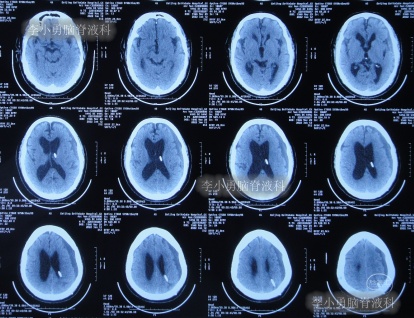

出院后再次转住入当地的第1家医院进行康复治疗,在该院康复治疗半年多的时间,不但没有持续好转,反而再次腰疼,走路不稳,且还出现了尿失禁的持续加重症状;治疗期间曾6次查头部影像(图-13、图-14、图-15、图-16、图-17)均示脑积水不断加重的趋势。

图-13:2021年5月22日头部核磁

图-14:2021年6月2日头部核磁

图-15:2021年7月24日头部核磁

图-16:2021年8月28日头部核磁

图-17:2021年9月28日头部CT